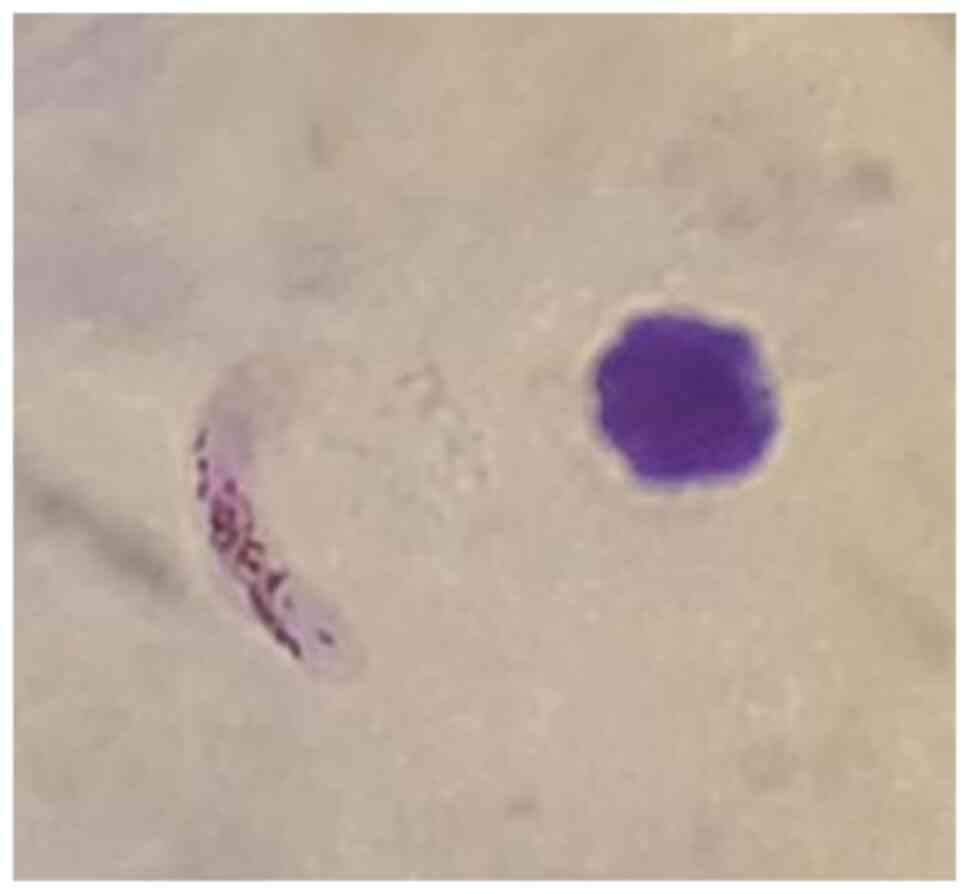

administered. After 24 h, malaria parasitemia was re-evaluated

revealing only the presence of P. falciparum banana-shaped

gametocytes (Fig. 3). The fever

disappeared together with clinical improvement and normalization of